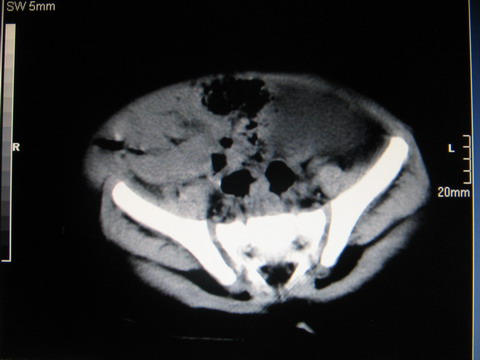

标题: PED0552:男1岁,双肾区CT

胎龄5个月时b超示左肾积水,现一岁后复查

左肾重度积水!

左肾重度积水!考虑肾盂输尿管交界处先天性狭窄或闭塞所导致

左肾重度积水.

左肾重度积水。

左肾重度积水(先天性左输尿管狭窄所致?)。

先天性左输尿管狭窄所致左肾重度积水。